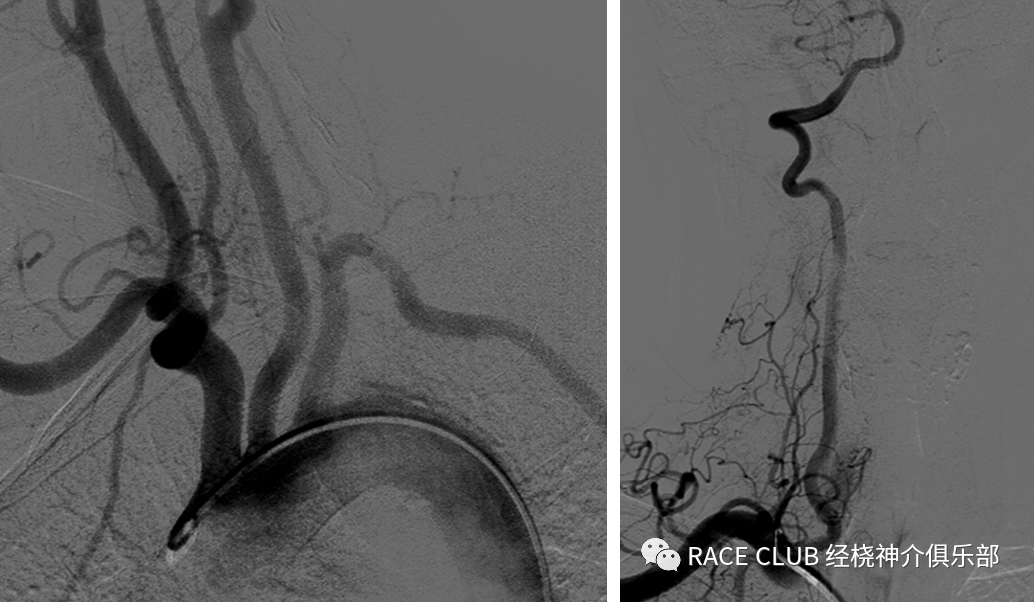

脑血管造影术目前是诊断脑血管病 变的“金标准”,尤其在全面动态观察血流情况、血管变异情况、侧枝代偿、Willis环情况、狭窄率计算等方面具有不可代替的作用。

弓上造影(股动脉入路)

•将单弯导管或西蒙导管头端送入血管鞘内,泥鳅导丝浸水后从y阀送入,透视下将导管导入,分别进入右锁骨下动脉、双侧颈总动脉(颈内动脉)、左锁骨下动脉造影

•侧位:(42)上端去头皮,下端露出分叉处,最好看到导管头端,图像在正中间

•正位:(27或31)矢状缝对齐,汤氏位,错开眉弓对大脑中动脉影响

造影导丝是什么全脑血管造影术_https://www.jmylbn.com_新闻资讯_第12张

•正位:(48)矢状缝对齐,稍汤氏位,上端平人字缝,下端露出椎动脉开口,看到导管头

•侧位:(31)左侧平枕骨隆突,下平2/3椎体